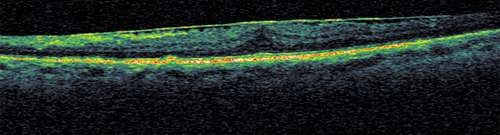

Retina anjiyografisi ve OCT (Optik koherenz tomografi) teşhisi koymamız ve tedaviyi planlamamız için yeterlidir.

Görme merkezinde retina önü zar oluşumunun OCT görüntülemesi

Ameliyat öncesi görme merkezindeki retina önü zar oluşumu